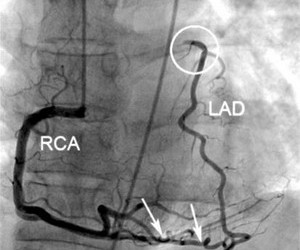

Uneori există posibilitatea ca bypass-ul să se formeze natural, adică să se recruteze colaterale pentru compensarea unei ocluzii și salvarea de la infarctizare a unei zone de miocard ischemic. Circulația colaterală se formează atât în ocluziile cronice, cât și în cele acute (prevenind transformarea unui NSTEMI în STEMI și evitând necesitatea de revascularizare în STEMI).

Referințe: Natural Bypasses Can Save Lives, foto: Circulation